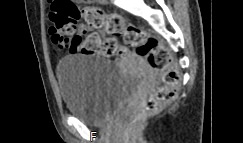

Мультиспиральная КТ мочевого пузыря является частью протокола обследования органов малого таза. Это высокоинформативный рентгенологический метод исследования, позволяющий детально визуализировать мочевой пузырь, нижнюю часть мочеточников, внутренние половые органы, прямую кишку.

Зачастую подобное исследование проводится при мочекаменной болезни (МКБ) для выявления конкрементов, определения их положения, размеров и плотности. Локализация конкремента существенно влияет на терапевтическое лечение МКБ, а наличие дивертикулов стенки мочевого пузыря на возможность самостоятельного выхода камня.

Также при данном исследовании возможно выявить утолщение стенки мочевого пузыря, что при диффузных изменениях может соответствовать проявлениям цистита, а локальные или неравномерные утолщения – характеризовать патологический процесс обусловленный новообразованиями.

Что позволяет увидеть КТ мочевого пузыря

- цистит;

- дивертикулы мочевого пузыря

- цистоцеле

- уретероцеле

- варианты строения мочеточников

- камни мочевого пузыря;

- травмы, разрывы и растяжения органа;

- опухолевые новообразования.